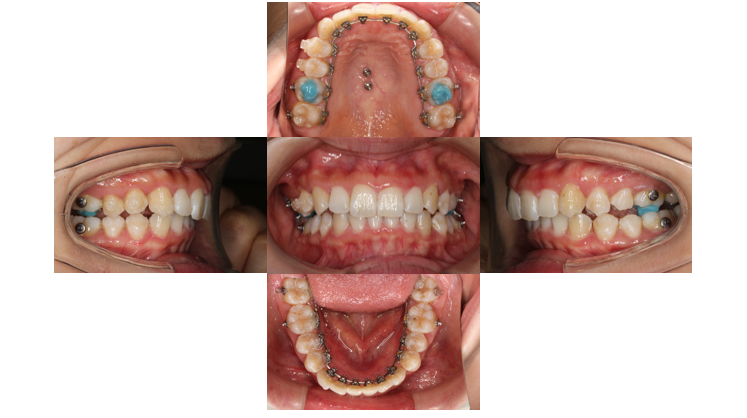

6か月経過

噛み合わせを良くするためにボタンを使用し、ゴムかけをしていきます